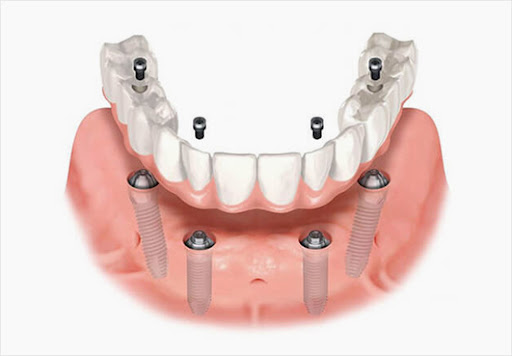

대부분의 사람들이 흔히

‘임플란트 틀니’ 라 알고계실 수 있는데요,

환자에게 필요한

최소한의 임플란트 식립을 통해

한 개의 아치 형태 보철을 연결하는 술식을 뜻합니다.

틀니가 불편하신 분이나

전악 식립에 대한 비용적인 부담이 있는

환자들에게 유용하게 적용시킬 수 있습니다.

아무래도 적합도에 따라

들썩거리거나 빠지는 불편함도 없고

잇몸을 짓누르는 통증도 적은 데다가

픽스처 식립 개수가 적다 보니

합리적인 금액으로 저작 기능을 회복할 수 있어

선호하시는 분들이 많답니다.

6개월 정도 모든 진료를 마치고

어버트먼트를 체결한 뒤

최종 보철을 올려드린 모습입니다.

(위 사진은 예시이며,

이해하시는데 좀 더 수월하실 것 같아

준비해봤습니다.^^)